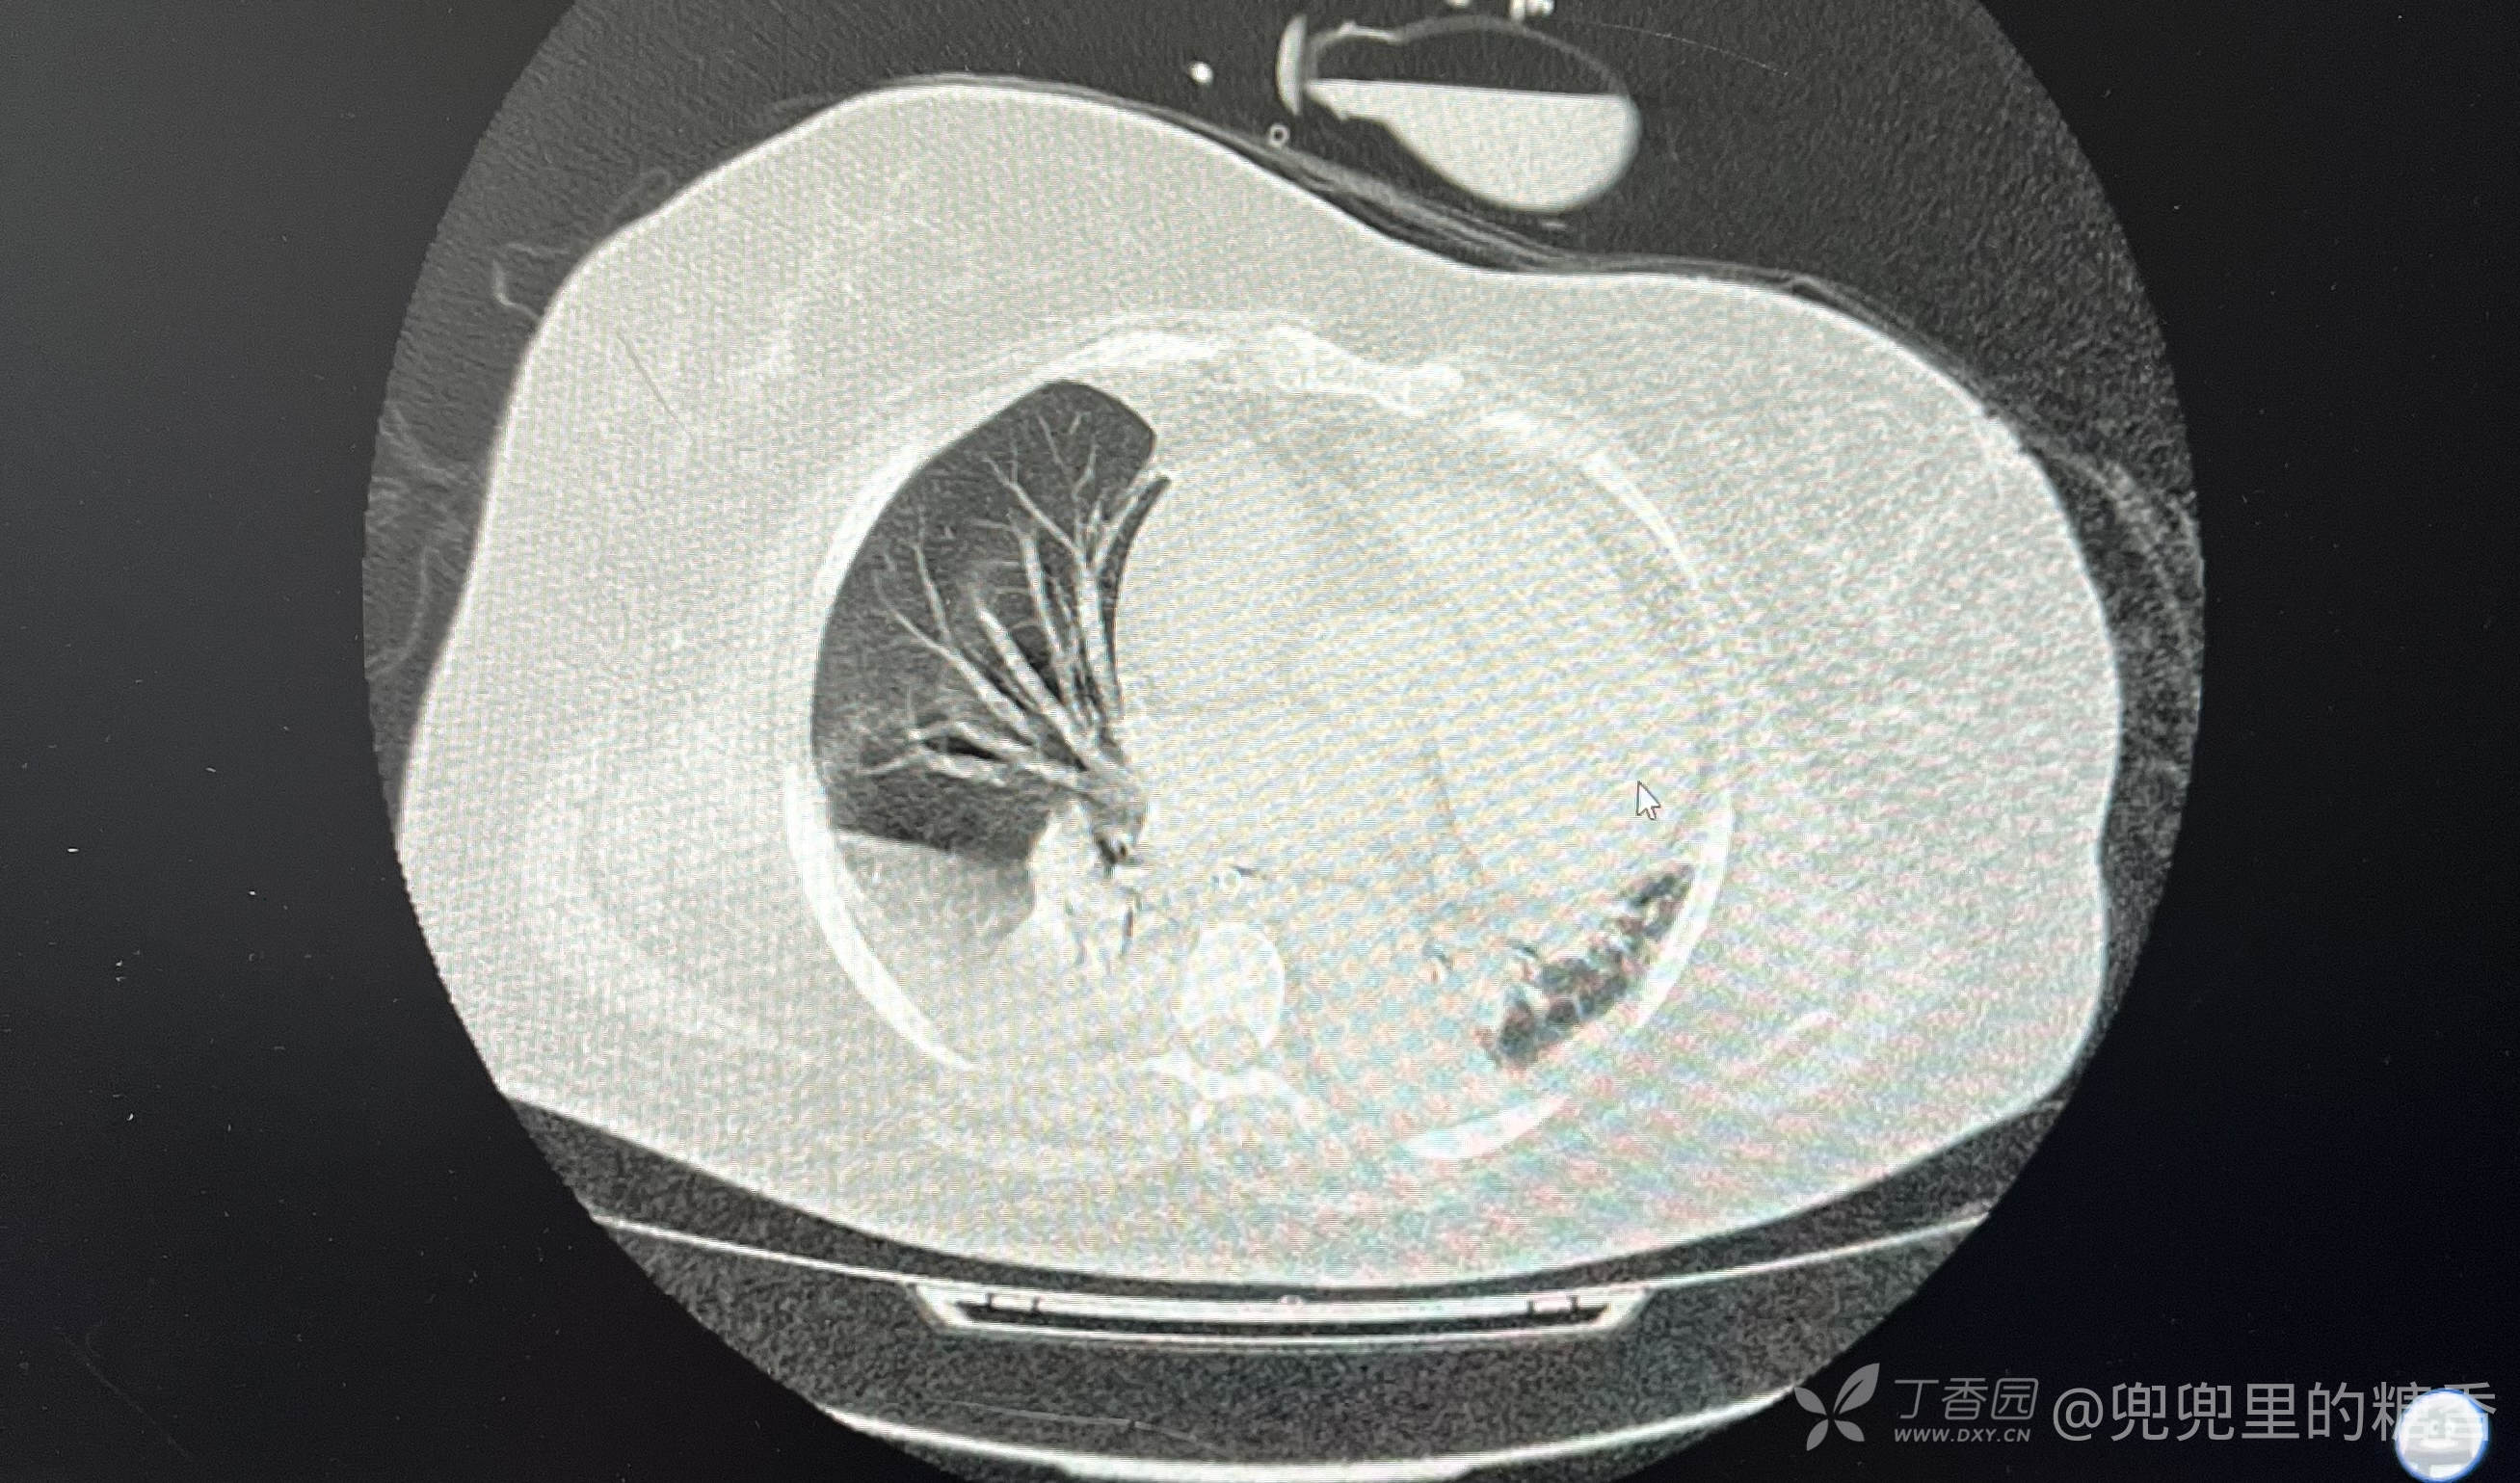

患者肥胖症,106公斤,近2月来体重增加10公斤,既往高血压病史15年,半月前出现乏力,加重一天入院。入院前一晚上出现意识障碍,入院是全身体浮肿,浅昏迷,吸氧10升/L,血氧饱和度80%,血压155/90mmHg,院外肺部CT提示肺部炎症,心脏扩大,考虑高心病并心力衰竭,呼吸衰竭,肺部感染